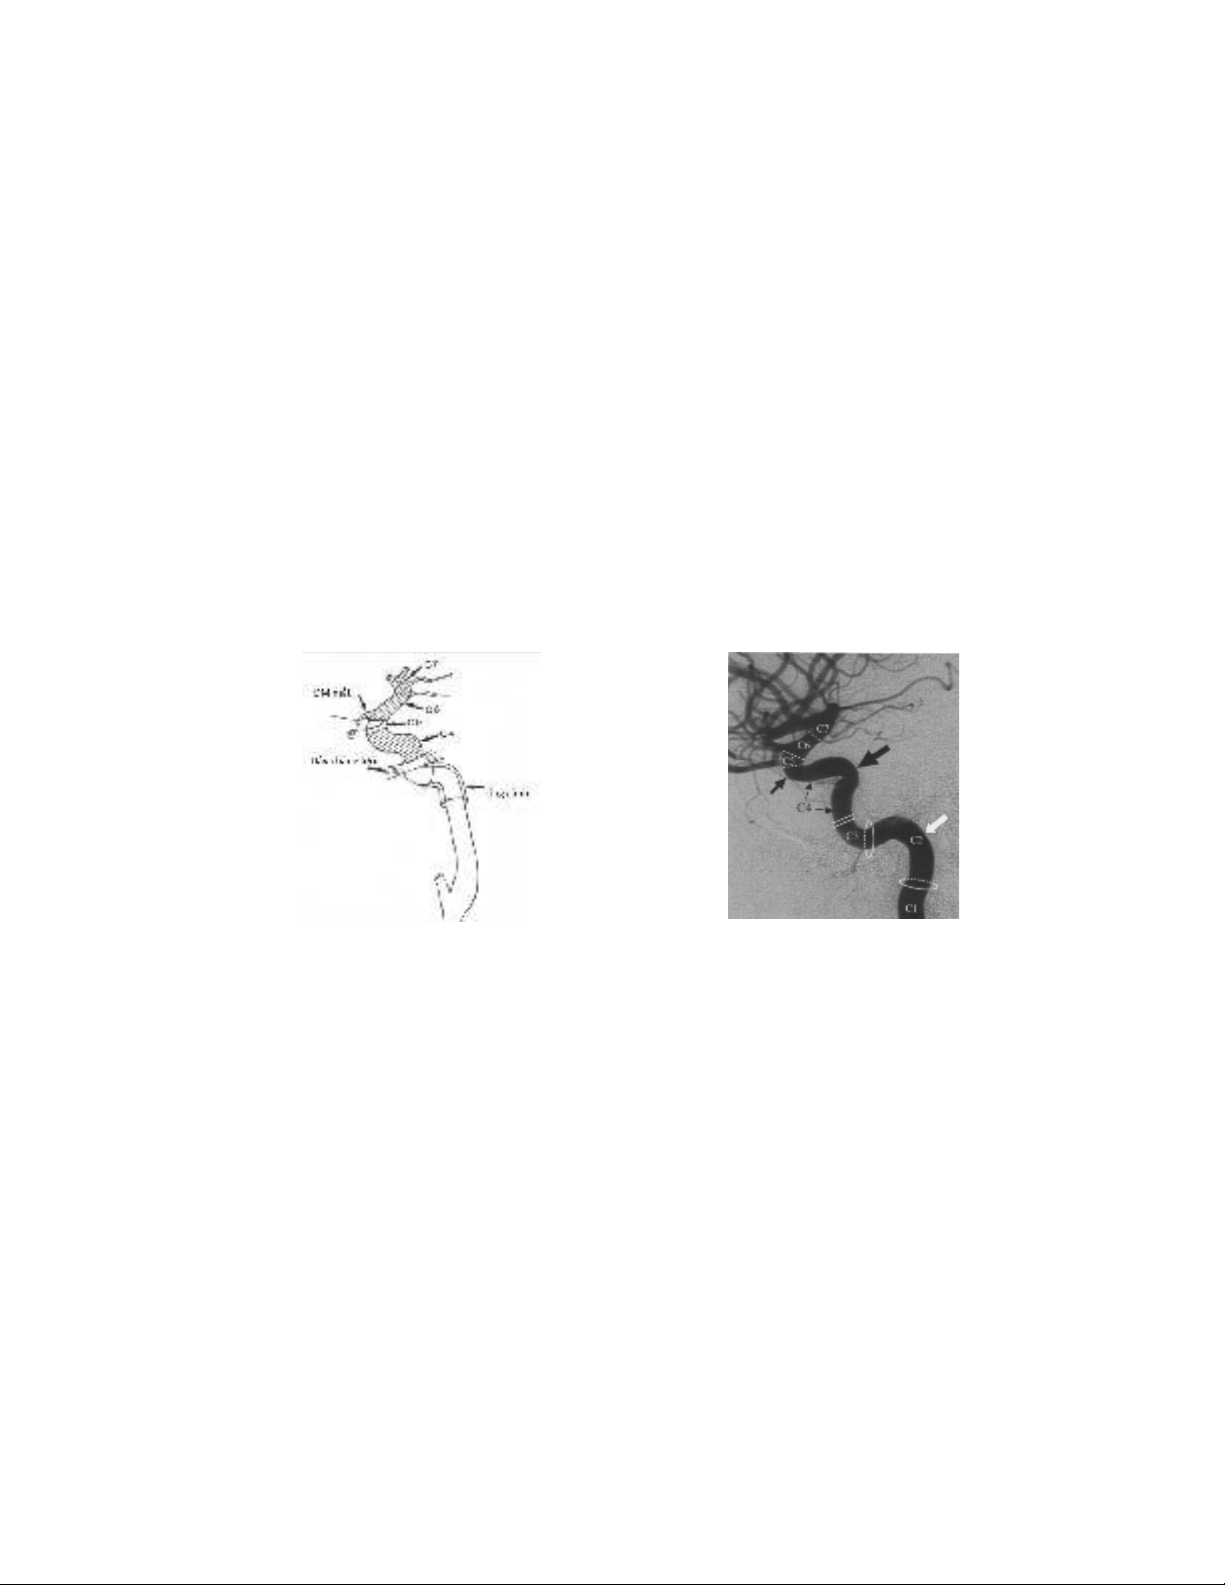

a b

Hình 1.1: Phân chia đoạn của ĐM cảnh trong trên sơ đồ (a) và trên hình ảnh

chụp mạch số hóa xóa nền (b) [1].